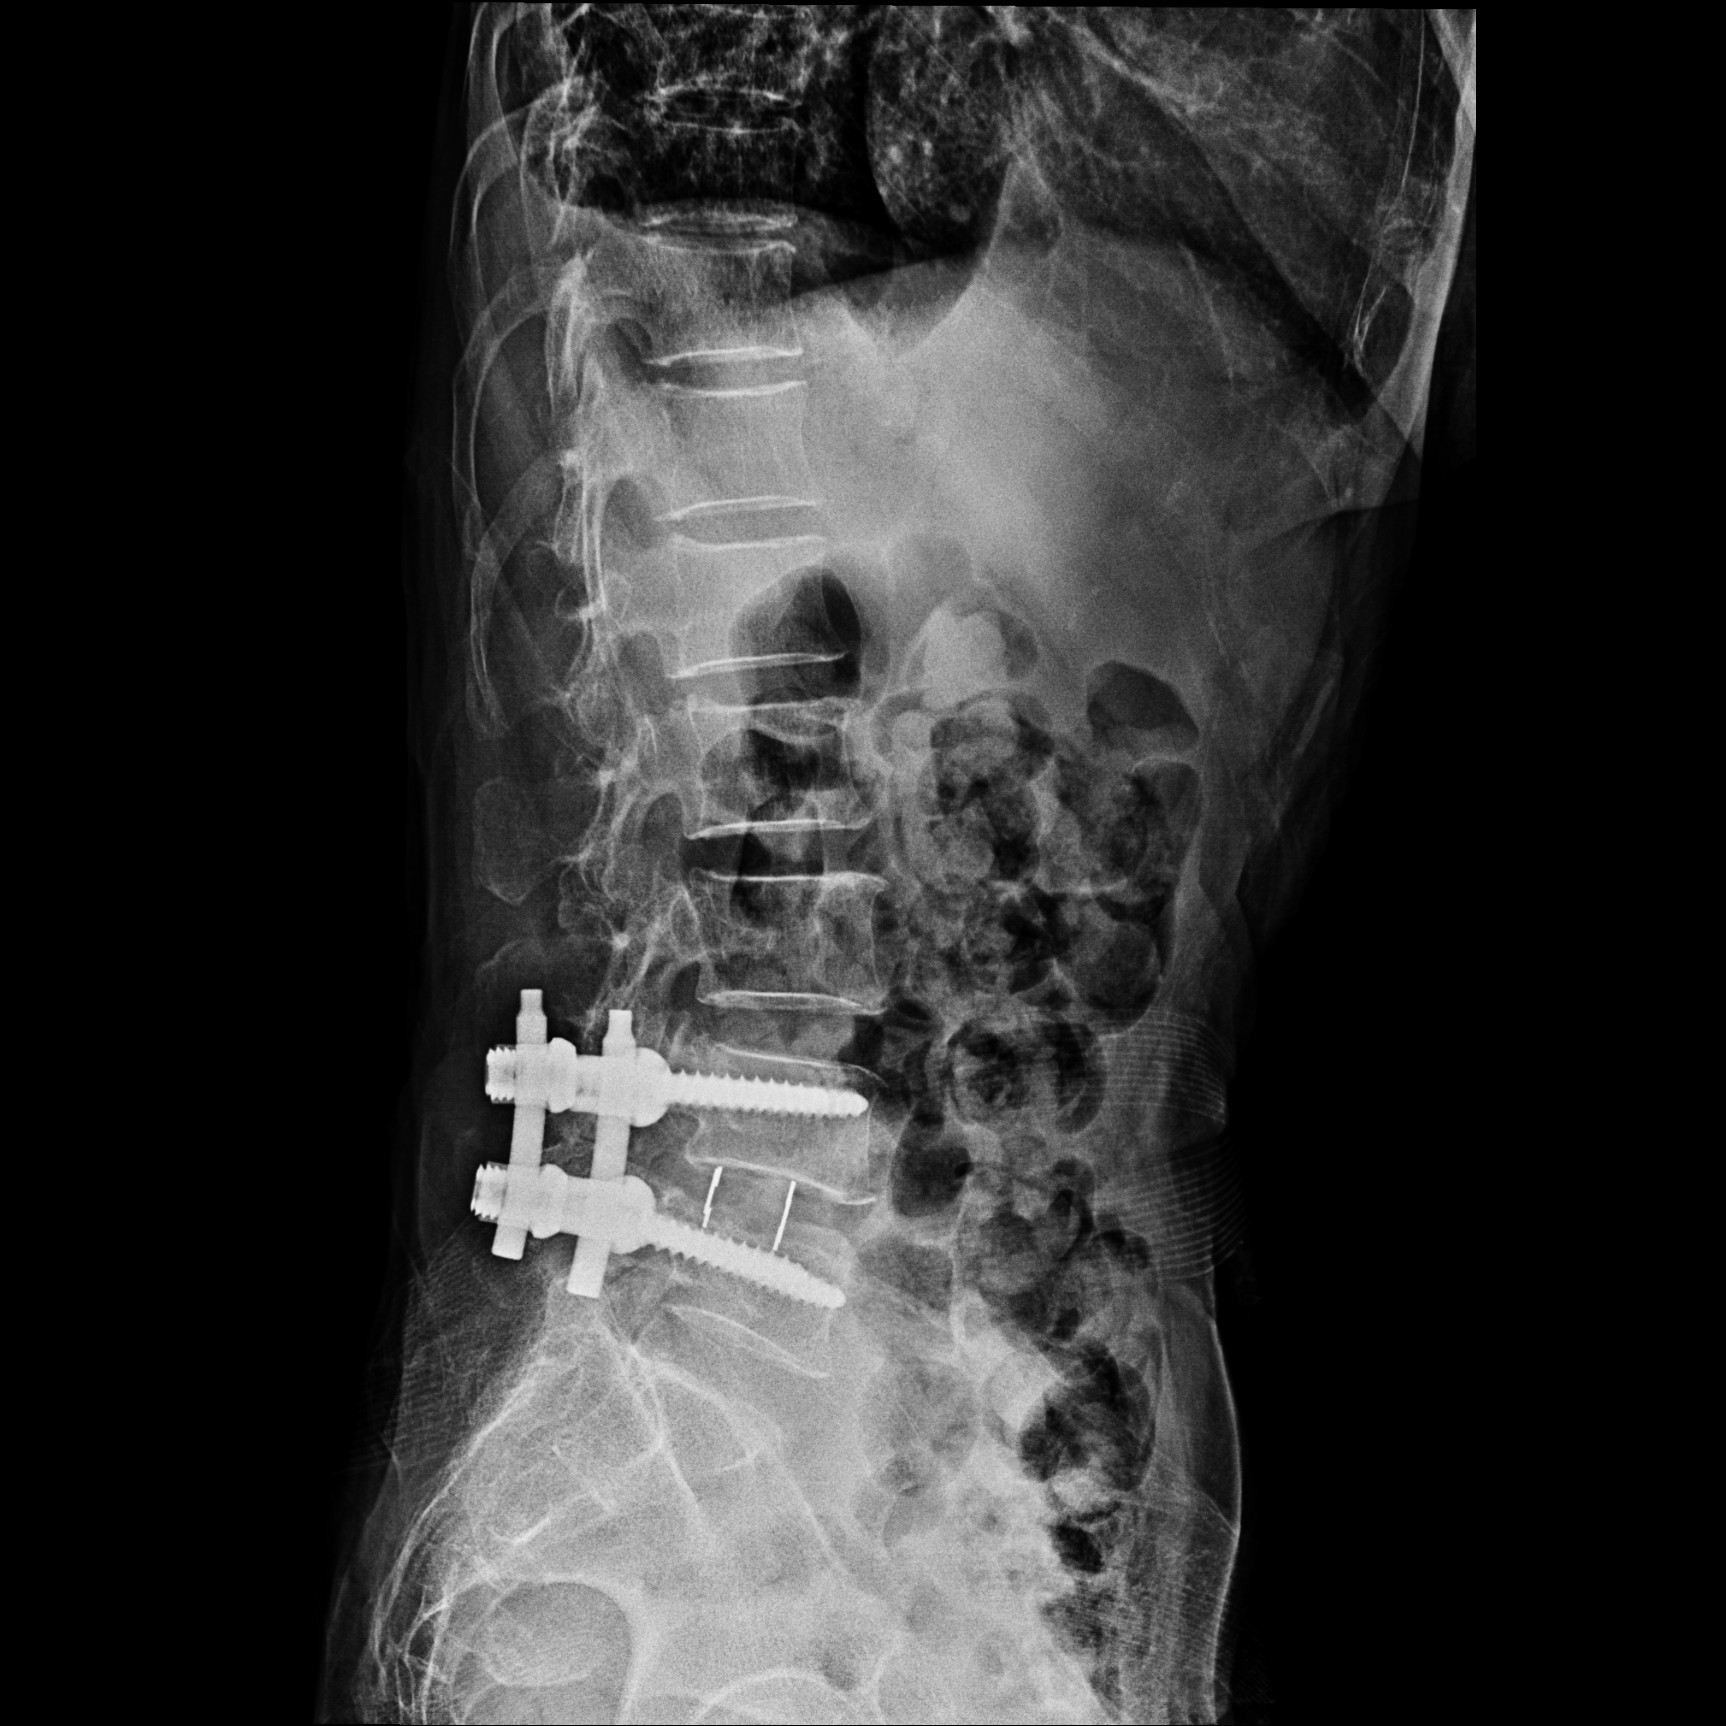

患者术后正面和侧面X-ray

我院脊柱外科团队经过科室会诊讨论后,决定采用微创腰椎斜外侧入路椎间融合术。以王剑龙主任、苗惊雷副主任医师、陈世杰主治医师及李劲松博士后组成的治疗团队在张朝跃教授、詹瑞森教授的指导下仔细分析病人的临床资料与影像学特点,进行了精心地术前准备,于12月4日上午9点开始手术。术中仅在患者左侧腹部椎体前缘2横指处做了一个约4cm的纵切口即可抵达手术部位,按照肌纤维方向钝性分离腹壁肌肉后到达腰椎侧前方,在主动脉与腰大肌间隙之间放置扩张通道,处理椎间隙并恢复间隙高度,使滑脱复位,放置合适大小的融合器。后路同样应用微创方法植入椎弓根螺钉固定。患者术后6天下床,腰痛及双下肢麻木症状完全消失。